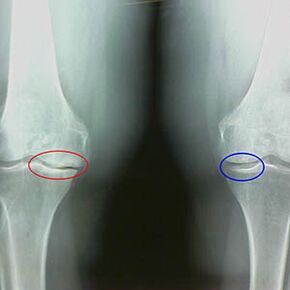

Les premières caractéristiques du faisceau X de la deuxième étape de l'arthrose du genou:

- Les bords pointus des tubercules internes sur le tibia, à laquelle la bande définie par la croix est attachée;

- Rétrécissement de l'écart commun du côté médial;

- Les bords pointus du condyle osseux sur les côtés médiaux, moins souvent dans le côté - selon le développement du valgus ou la déformation de la connexion variante.

Pour la deuxième étape de Larsen Le rétrécissement de l'écart commun de plus de 50% est caractéristiqueCependant, cela ne peut être vérifié que dans la dynamique ou en comparaison avec un ininterrompu des articulations.